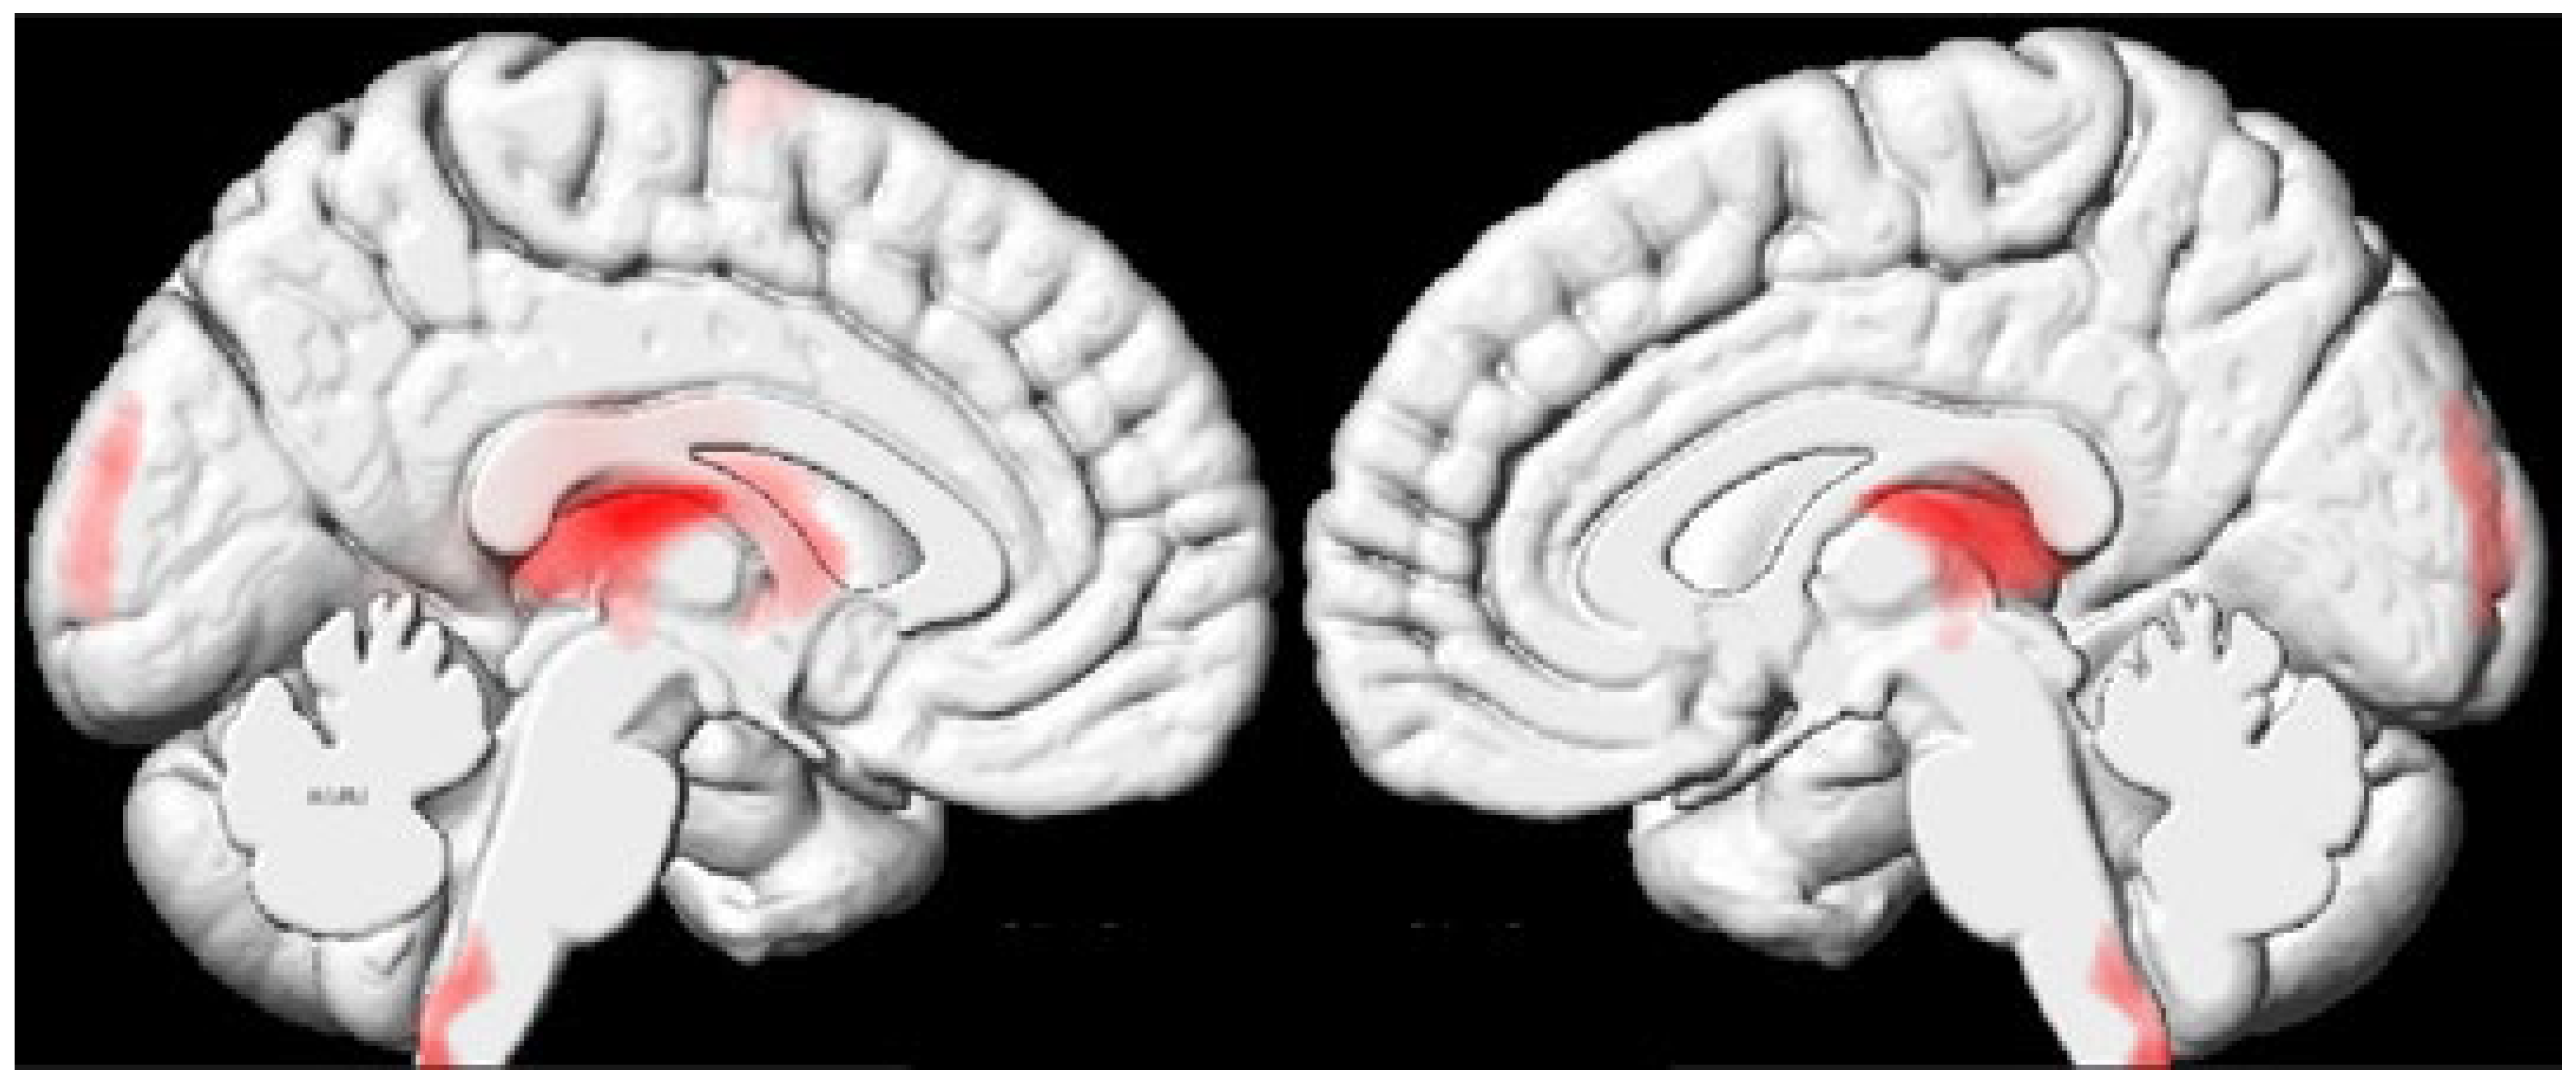

| 2 | −10 | −20 | 14 | −8 | −23 | 12 | 17533 | Thalamus (bilateral) and caudate nucleus (left) |

3.1. Decreased Microstructural Integrity of the Thalamus